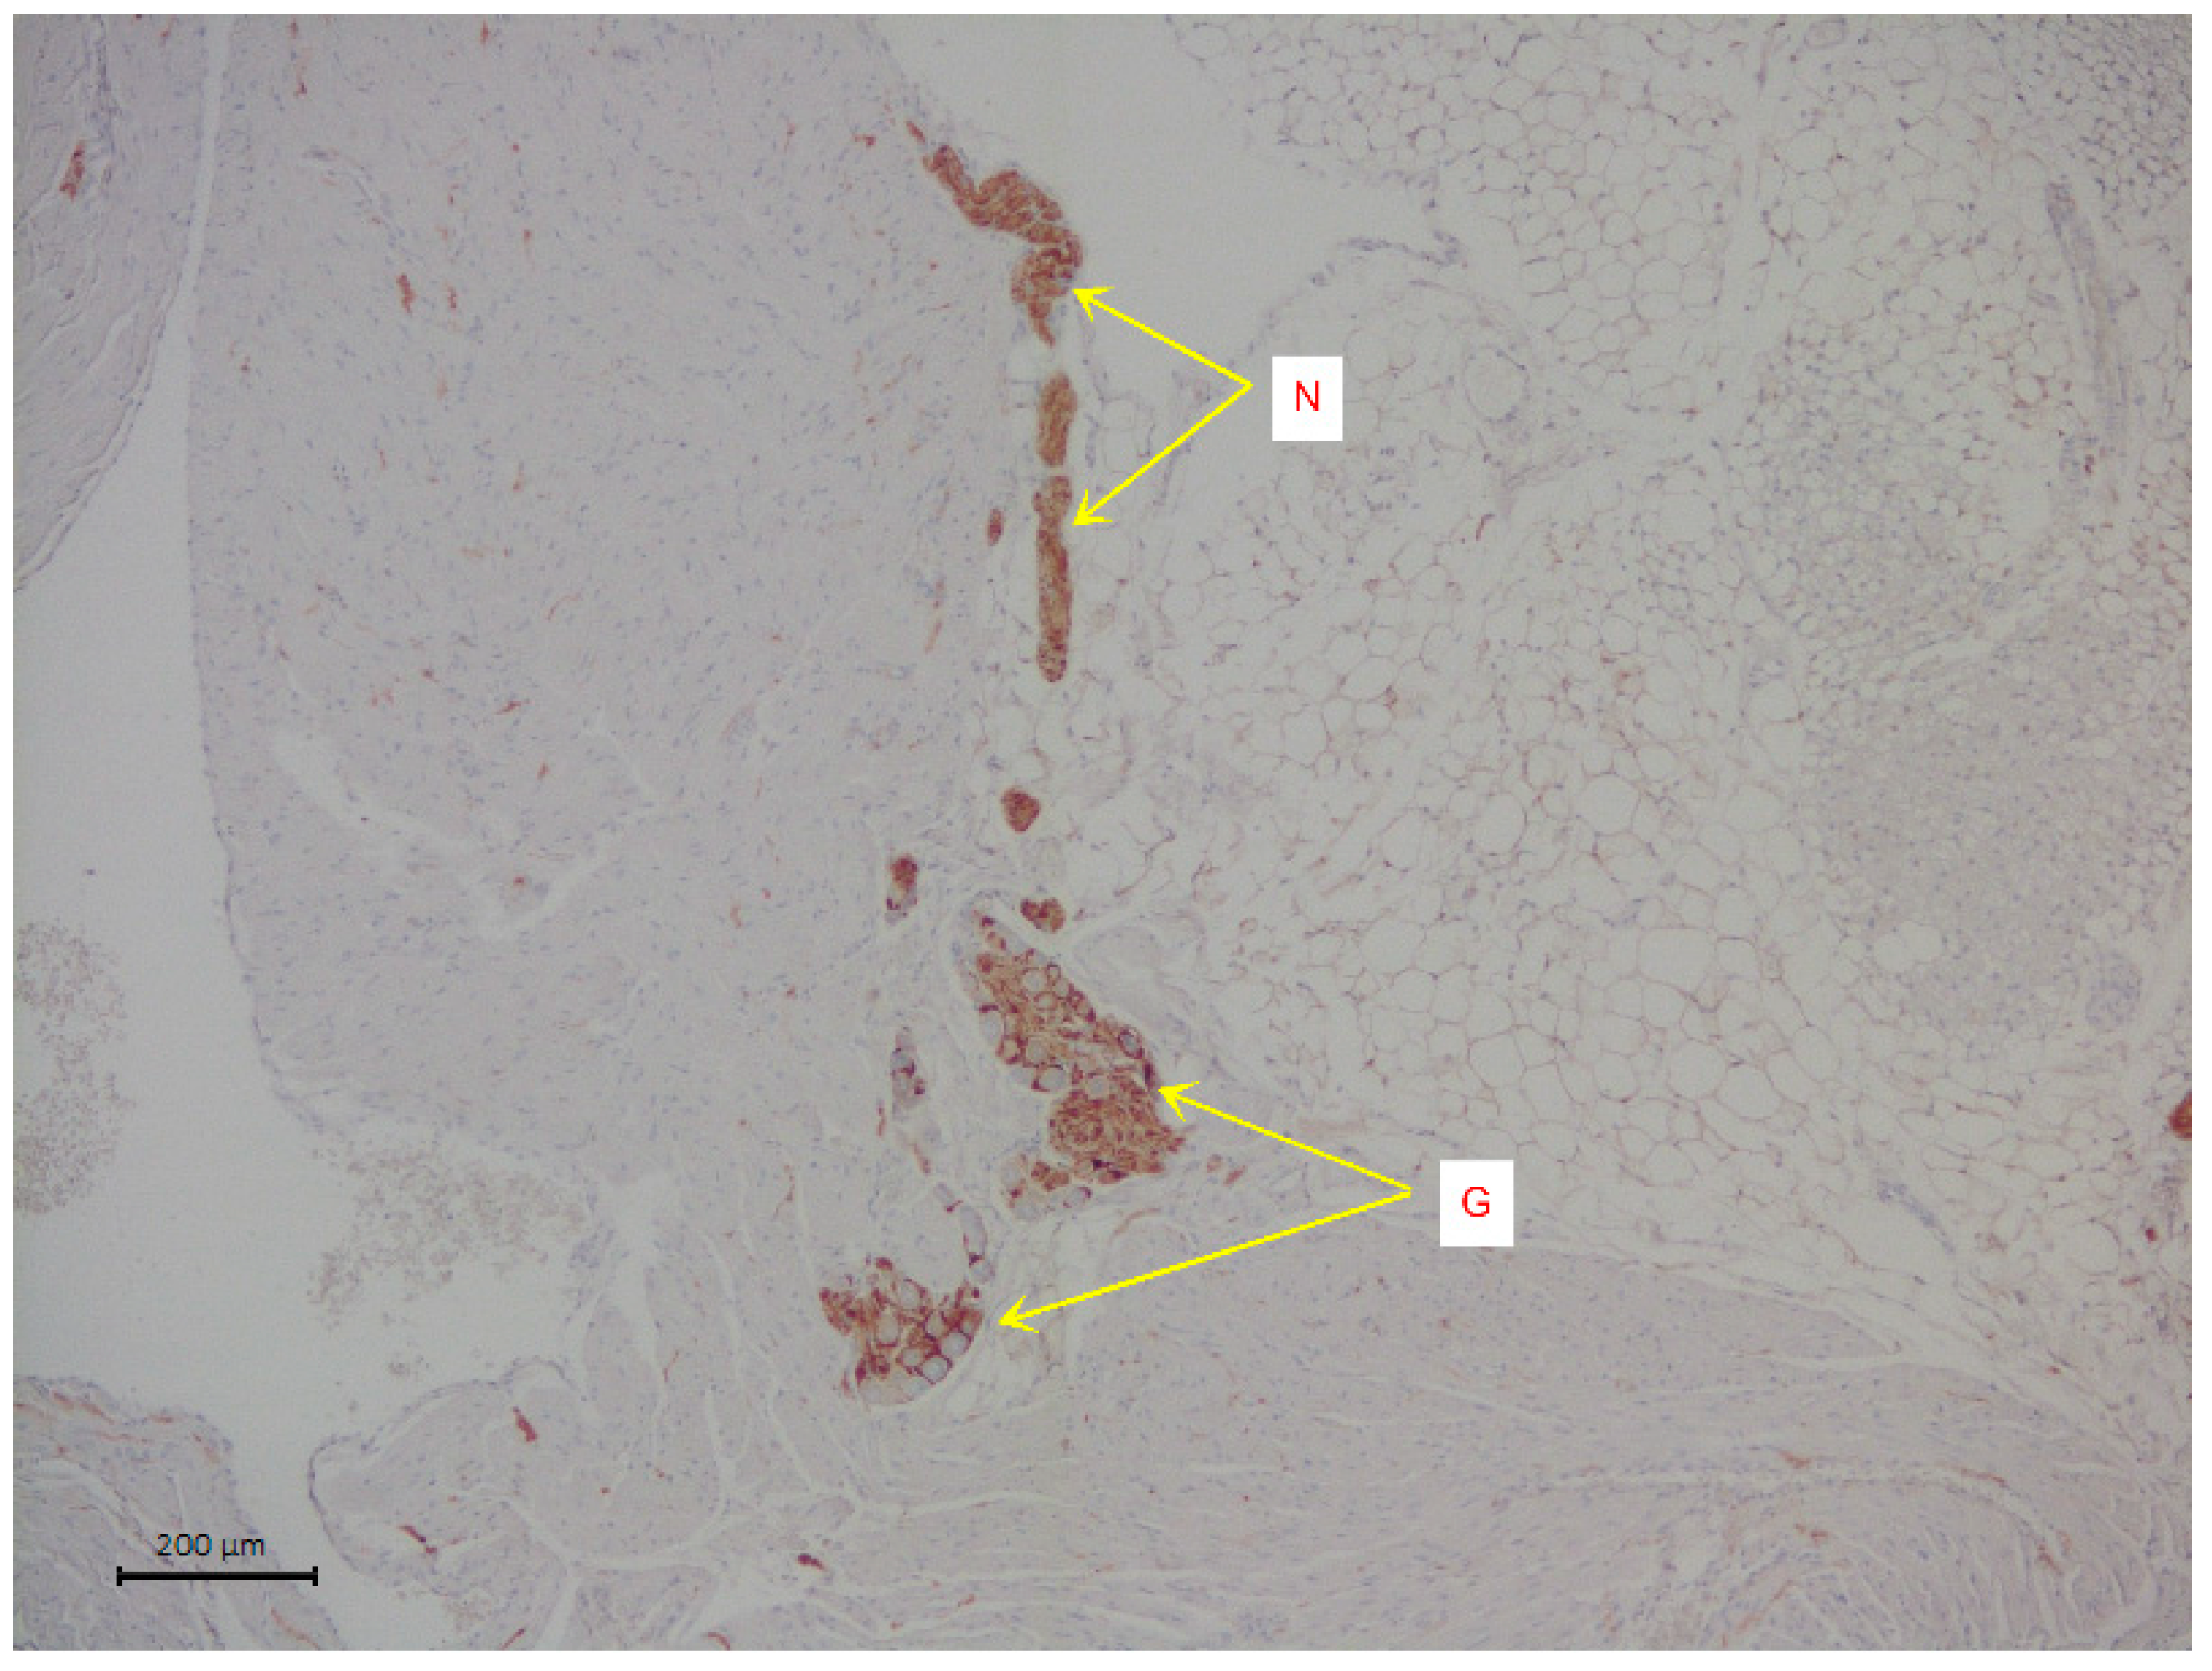

The slices were stained with hematoxylin and eosin. Immunohistochemical analysis was used to visualize the nervous tissue elements of the atrium. The cells of intramural parasympathetic ganglia were determined using staining with rabbit recombinant antibodies against the protein S100 beta [EP1576Y], a marker of astrocytes ab52642 (Abcam, Cambridge, UK). Incubation with S100 beta antibodies was carried out at a dilution of 1:2000 in a Leica Autostainer 720 during 30 min using the Novolink Max Polymer Detection system. The diaminobenzidine Novolink Max Polymer Detection System (LEICA Biosystems, Deer Park, Illinois, USA) was used to visualize the antibody fixation loci (see Figure 1). The slices were additionally stained with Mayer hematoxylin in the Leica Stainer.

Figure 1. A representative image of intramural neural structures of rat right atrium. The arrows indicate parasympathetic nerve ganglion (G) and parasympathetic neural fibers (N). Immunohistochemical analysis on S100 b.